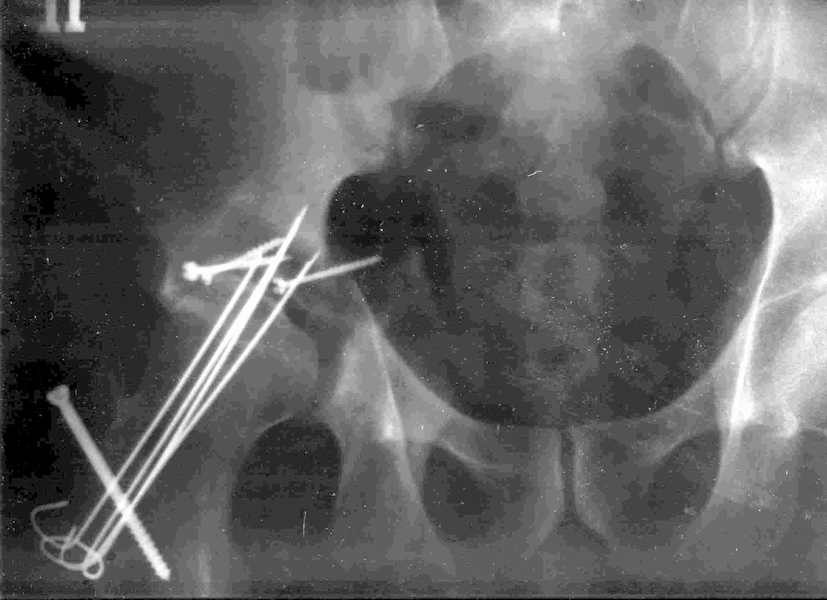

Xray1

Xray2

Высылаю прямой обзорный и косой подвзошный снимки, косой запирательный неудовлетворительного качества.

Было бы существенным посмотреть обзорную R-грамму до операции. По данным послеоперационных снимков и КТ имеется низкий двухколонный перелом или

высокий Т-образный перелом с отрывом свода. Для уточнения необходиы косые проекции (Judet). Весь ли седалищный нерв молчит или только м/б порция?

Представленный перелом вертлужной впадины характеризуется нарушением непрерывности тазового кольца, обусловленный переломом передней и задней колонн, вполне возможно и с повреждением weightbearing surface- по прямой рентгенограмме сложно однозначно судить, а представленные томограммы не захватывают несущую поверхность впадины. Экспресс протезирование однозначно не показано - фиксировать ацетабулярный компонент не к чему, а цемент *уйдет* в зоны перелома. Достаточно обширное вмешательство должно быть направлено на восстановление целостности тазового кольца(передний забрюшинный доступ) и фиксация реконструктивной пластиной, после чего пациент поворачивается на бок или на живот и на тракционном столе из заднего доступа фиксируется задняя колонна реконструктивной пластиной. Для репозиции фрагментов нужно иметь тазовые зажимы (pelvic reduction clamps), без которых достичь желаемого результата технически сложно. Оптимальное время хирургии через неделю, 10 дней , когда общее состояние больного стабилизируется и закончено активное кровотечение из отломков. Хорошо бы иметь cell saver для таких случаев, а если нет - интраоперационная гемотрансфузия донорской крови.